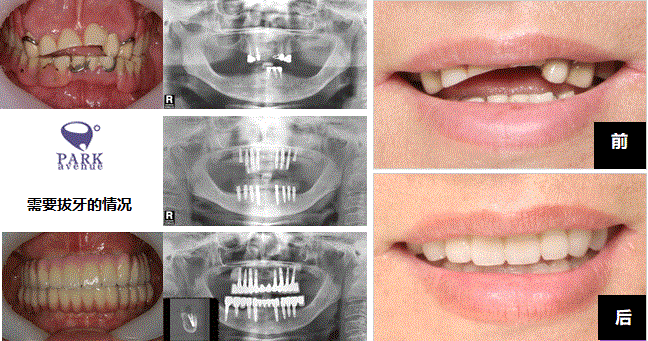

没有牙齿的患者也别担心!我们PARK AVENUE的缺牙种植牙手术是大部分牙齿也没有的人也可以手术种植牙。使用我们的技术秘诀牙龈骨头不足,细细的情况也制作固定性口康假体治疗的缺牙种植牙手术。

牙齿完全没有的时候也使用种植牙可以离开假牙。使用7~12个左右的种植牙制作口康假体,可以跟正常牙齿一样使用。咬的力也比使用假牙的时候强,而且不用带假牙的优点也有。通过PARK AVENUE的技术秘诀细心地考虑牙齿的状态和骨头吸引程度植立正确和安全的种植牙。